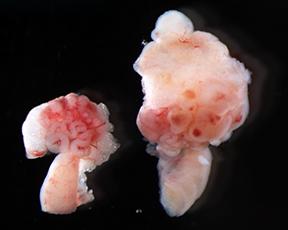

January 27, 2015 CHAPEL HILL, NC - In the battle against ovarian cancer, UNC School of Medicine researchers have created the first mouse model of the worst form of the disease and found a potential route to better treatments and much-needed diagnostic screens.

"It's an extremely aggressive model of the disease, which is how this form of ovarian cancer presents in women," said Magnuson, who is also a member of the UNC Lineberger Comprehensive Cancer Center. Not all mouse models of human diseases provide accurate depictions of the human condition. Magnuson's mouse model, though, is based on genetic mutations found in human cancer samples.

Mutations in two genes -ARID1A and PIK3CA - were previously unknown to cause cancer. "When ARID1A is less active than normal and PIK3CA is overactive," Magnuson said, "the result is ovarian clear cell carcinoma 100 percent of the time in our model."